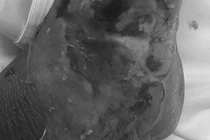

Tuy nhiên, chỉ sau một tháng, tình trạng chuyển biến xấu, vùng cẳng chân trái sưng tấy đỏ, viêm tấy lan từ bàn chân lên gần hết cẳng chân, xuất hiện nhiều bóng nước và phù nề mô mềm. Gia đình vội đưa bà vào Trung tâm Y tế trong tình trạng nhiễm trùng nặng.

Tại đây, bác sĩ chẩn đoán bà H. bị nhiễm trùng lan tỏa cẳng chân trái và được tiến hành phẫu thuật xử trí vết thương, làm sạch ổ nhiễm kết hợp điều trị kháng sinh tích cực.

Hiện sức khỏe bệnh nhân đã ổn định, tuy nhiên nếu nhập viện chậm hơn, nguy cơ hoại tử hoặc phải cắt bỏ chi là rất cao.